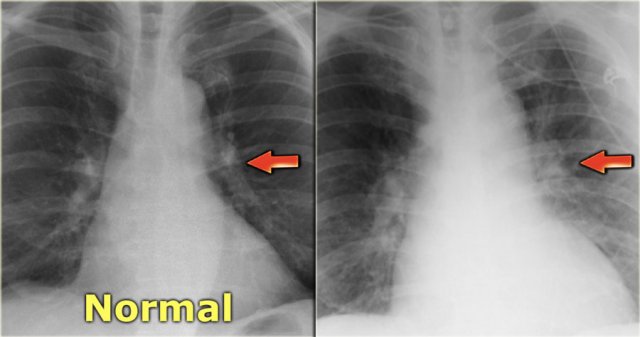

Views of the upper lobe vessels of a patient in good condition (left) and during a period of CHF (right). Notice also the increased width of the vascular pedicle (red arrows). Views of the upper lobe vessels of a patient in good condition (left) and during a period of CHF (right). Notice also the increased width of the vascular pedicle (red arrows).

Stage I - Redistribution

In a normal chest film with the patient standing erect, the pulmonary vessels supplying the upper lung fields are smaller and fewer in number than those supplying the lung bases.

The pulmonary vascular bed has a significant reserve capacity and recruitment may open previously non-perfused vessels and causes distension of already perfused vessels.

This results in redistribution of pulmonary blood flow.

First there is equalisation of blood flow and subsequently redistribution of flow from the lower to the upper lobes.

The term redistribution applies to chest x-rays taken in full inspiration in the erect position.